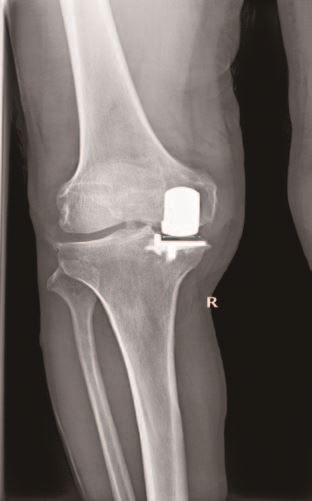

67岁的王大爷三年前出现右膝关节疼痛,经过多次口服药物、理疗等保守治疗,效果越来越不好,如今行走200-300米左右就疼痛难忍,严重影响日常生活,于是在家属的陪同下来到我院就诊。经X光片检查显示,王大爷术前膝关节活动度伸直5°,屈曲120°,轻度内翻畸形,被确诊为右膝骨性关节炎,医生建议手术治疗。5月20日,医生们为其实施了人工膝关节单髁置换手术,手术进行顺利,术后王大爷的手术切口愈合较好,膝关节内翻畸形纠正,1周内经过锻炼膝关节伸直5°,屈曲110°,王大爷对手术及术后功能恢复非常满意。

基于人工膝关节单髁置换的优点,我院骨科积极引进积水潭医院矫形骨科技术,使用牛津OxfordIII代单髁假体成功开展膝关节单间室骨性关节炎单髁置换术,术中切除骨量小,术后患者不需要输血,易于康复,治疗效果令人满意,深受骨科医生和患者的青睐。